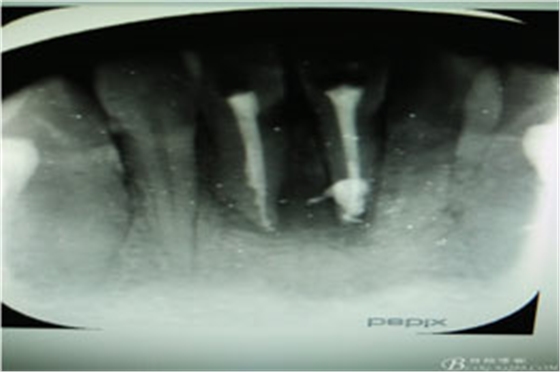

圖6.根管治療+樹脂充填后根尖片影像:31根尖1/3大量根充物溢出。因此必須同期根管外科治療